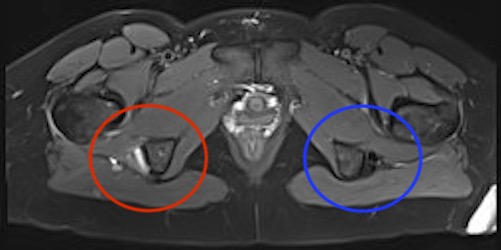

Proximal hamstring avulsion on right - red circle is retracted hamstring tendon, blue circle is normal insertion on left

Proximal hamstring tear on right (red circle), normal insertion on left (blue circle)